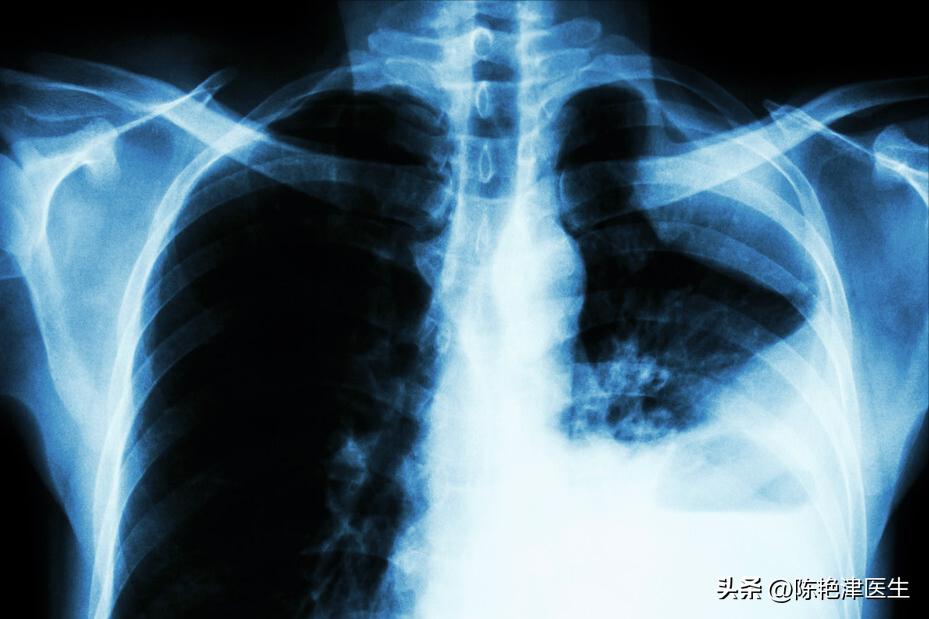

2. 肺鳞癌

肺鳞癌大约占肺癌发生率的50%,主要是发生在 支气管 部位的中央型肺癌。

肺部与空气接触的器官,容易接触外界的有害物质而病变。其中的 支气管覆盖有鳞状上皮细胞。

肺鳞癌常发生于在化工厂、冶炼厂等地工作的工人。他们的工作环境存在大量可吸入的 石棉、砷、铬等各种重金属 ,肺部与这些有害物质长期接触,容易导致支气管表面的鳞状上皮发生癌变。

表现在人体会有 咯血、胸闷、低热 等症状,进展至中晚期,癌细胞扩散至全身,发生其他脏器组织或功能的改变。

老年人应该定期筛查肺癌, 早期筛查手段是低剂量螺旋CT。建议有长期吸烟史或者有慢性的肺部基础疾病的老年人每年进行一次筛查。